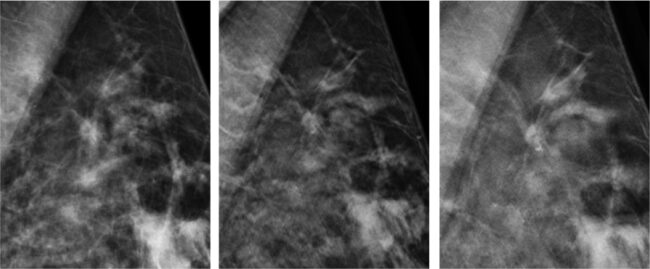

Minęło już niemal 8 lat od momentu, jak społeczności lekarskiej została przedstawiona pierwsza ocena kliniczna tomosyntezy piersi (RSNA, 2006). W tym okresie kilka tysięcy kobiet było poddanych temu szczególnemu badaniu, którego skuteczność i wartość kliniczna została potwierdzona w większości publikacji medycznych opublikowanych na przestrzeni ostatnich lat. Podczas skanowania z tomosyntezą wykonywanych jest wiele obrazów obiektu pod różnym kątem, obrazy te są następnie rekonstruowane…